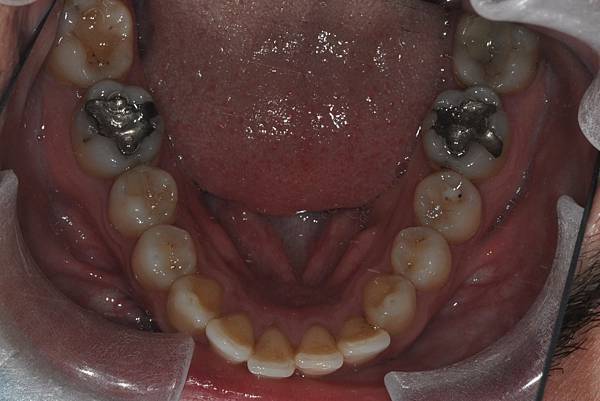

台灣的牙科醫療品質, 連外國人都說讚!此案例為深咬合併二級咬合 林醫師藉由正中上顎骨釘(HPPG technique)做上顎全齒列後移改善暴牙 讓本來五官就相當立體的艾先生,笑起來更燦爛了! 治療前/治療後-以上案例由林昇進醫師提供 分享到